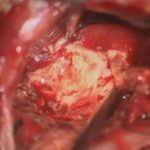

530

'24年5月

50代

小脳血管芽腫

頭蓋内腫瘍摘出術

No.’24_32 摘出 前

No.’24_32  摘出 中

No.’24_32 摘出 後